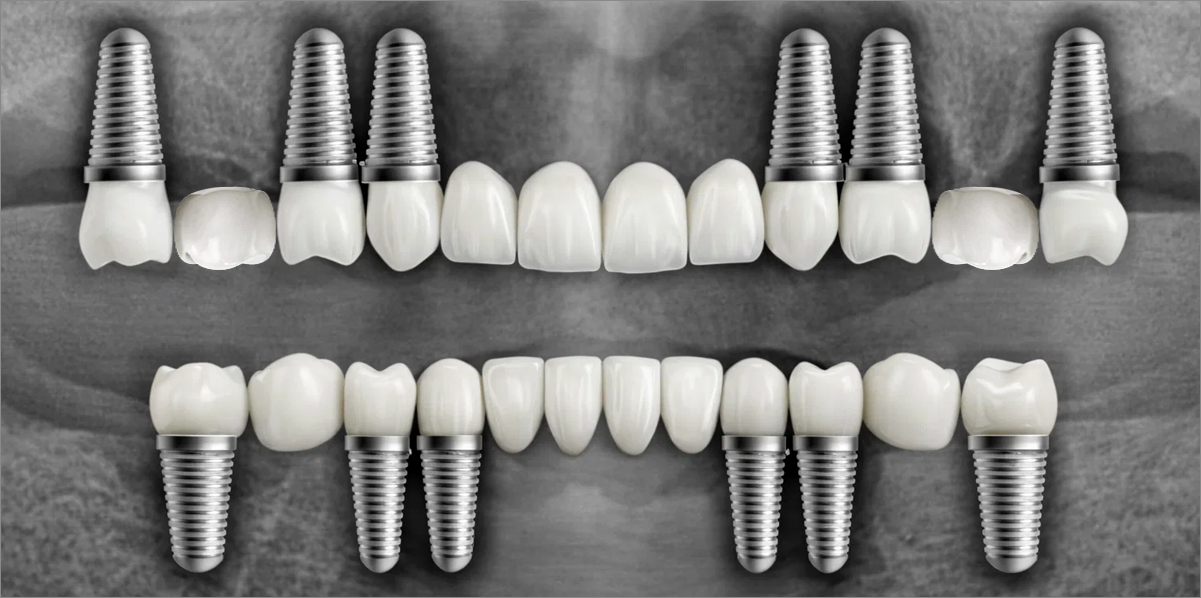

Full-mouth implant restoration is categorized into full placement or minimal placement approaches.

Full Placement

Using a method of placing 8–9 implants in the maxilla and 8 implants in the mandible, this approach fully restores all 28 natural teeth, creating an oral environment most closely resembling

natural dentition.

• 02

Minimal Placement

Using a method of placing 6–7 implants in the maxilla and 6 in the mandible, this approach restores both posterior and anterior teeth, efficiently rehabilitating the entire oral cavity.